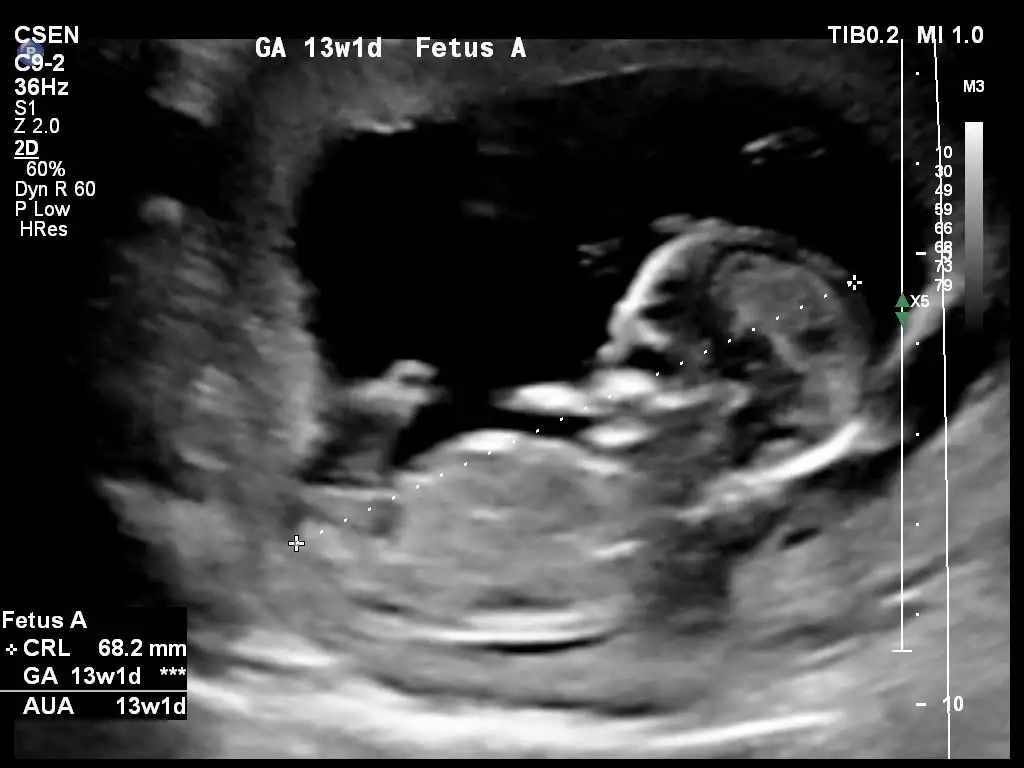

Ben 11 12 13 haftalara tahmin ediyorum burada nubunu göremedim sanki karşıya bakıyor gibi geldi banaIkra meyra merhaba biz bugün %80 oranla cinsiyeti öğrendik sen kararsız kalmış kıza benziyor demiştin atayım yine bugünkü fotoğrafları bakalım şimdi ne yorum yapacaksın

Erkek gibiMerhabaIkra meyra adete göre 11+4 ultrasonda 12+2 çıktı bize de cinsiyet yorumu yapabilir misin?Şimdiden teşekkürler

Doktorumuz bacak arasını gösterdi yan profilden de baktı ama verdiği ultrason fotoğraflarını gösterdiklerinden vermemişBen 11 12 13 haftalara tahmin ediyorum burada nubunu göremedim sanki karşıya bakıyor gibi geldi bana

Kesinleşince dönüş yaparsınızDoktorumuz bacak arasını gösterdi yan profilden de baktı ama verdiği ultrason fotoğraflarını gösterdiklerinden vermemiş%80 erkek dedi canım

12-13 hafta paylastinizmiDoktorumuz bacak arasını gösterdi yan profilden de baktı ama verdiği ultrason fotoğraflarını gösterdiklerinden vermemiş%80 erkek dedi canım

Bu ultrason fotoğrafı 13+4 canım en son 10+6 da gitmiştim onu gönderdim kıza benziyor ama emin olamadım gibi bişey yazmıştın.12-13 hafta paylastinizmi

Burada göremedim canım bacağı kapatmış son usgde başka USG varmı pekiBu ultrason fotoğrafı 13+4 canım en son 10+6 da gitmiştim onu gönderdim kıza benziyor ama emin olamadım gibi bişey yazmıştın.

Evet başka USG istedim emin değildimBu ultrason fotoğrafı 13+4 canım en son 10+6 da gitmiştim onu gönderdim kıza benziyor ama emin olamadım gibi bişey yazmıştın.

Malesef canım başka usg yokBurada göremedim canım bacağı kapatmış son usgde başka USG varmı peki

Tekrar baktım birinde parmağı denk gelmiş birinde karşıya bakan nubmu anlamadım emin olamadım gonlunuzdeki olsunMalesef canım başka usg yok ☺